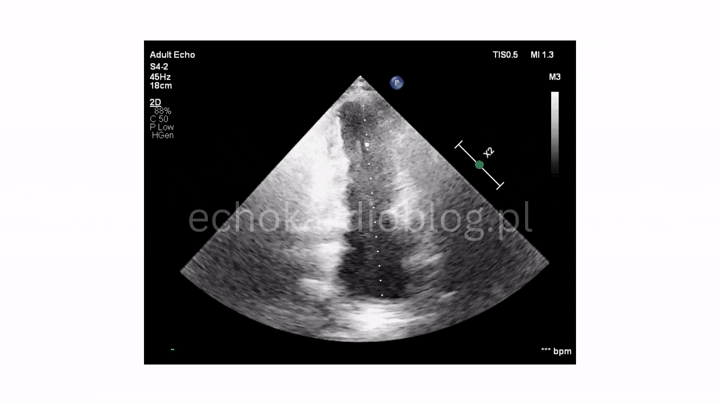

ciężka niedomykalność płucna w projekcji podmostkowej

dwie długie i bardzo ruchome wegetacje na płatkach zastawki płucnej – pr podmostkowa w osi krótkiej

CW Doppler przez zastawkę pnia płucnego – szybki spadek pędkości fali zwrotnej wskazuje na ciężką niedomykalność płucną